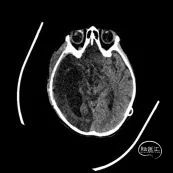

术后第1天